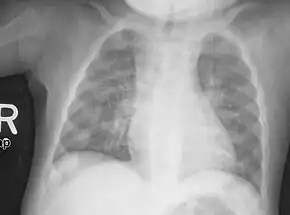

An X-ray or radiograph of an advanced patient with rickets tends to present in a classic way: the bowed legs (outward curve of long bone of the legs) and a deformed chest. Changes in the skull also occur causing a distinctive "square headed" appearance known as "caput quadratum".[14] These deformities persist into adult life if not treated. Long-term consequences include permanent curvatures or disfiguration of the long bones, and a curved back.[15]